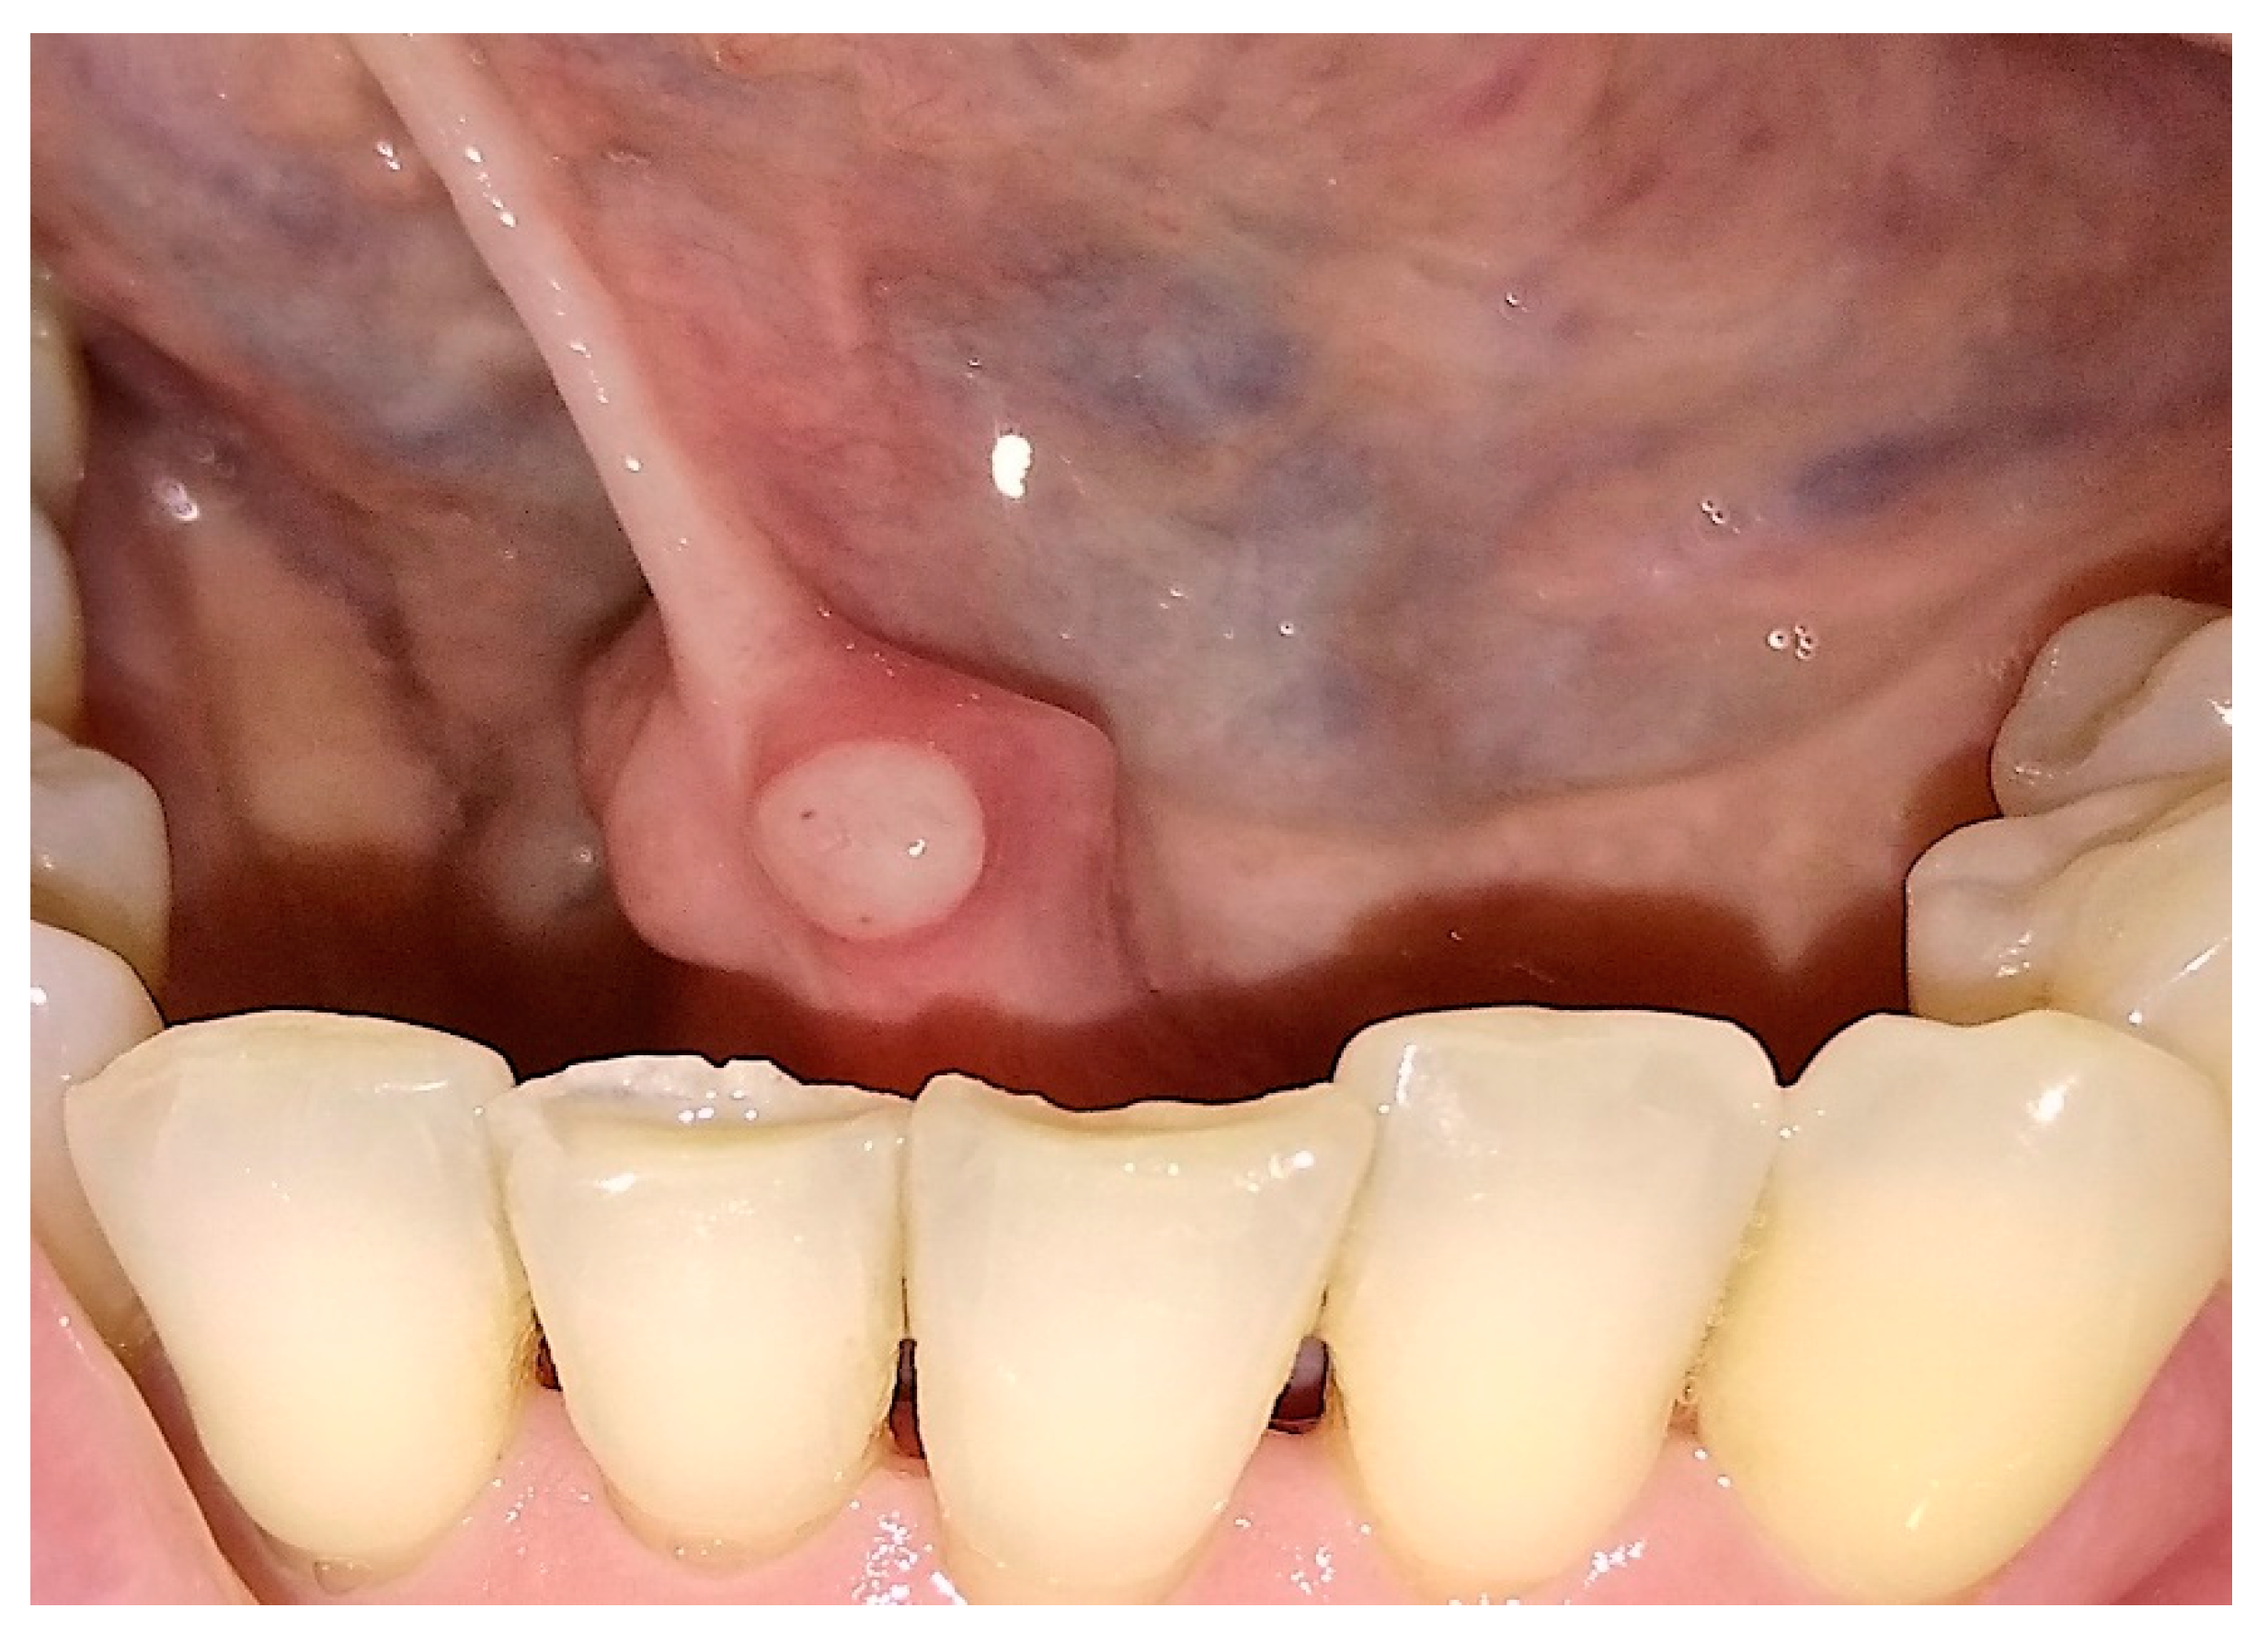

Photobiostimulation Therapy in Non-Responsive Oral Ulcerative Aftosis: 3 Cases Reports †

3. Results